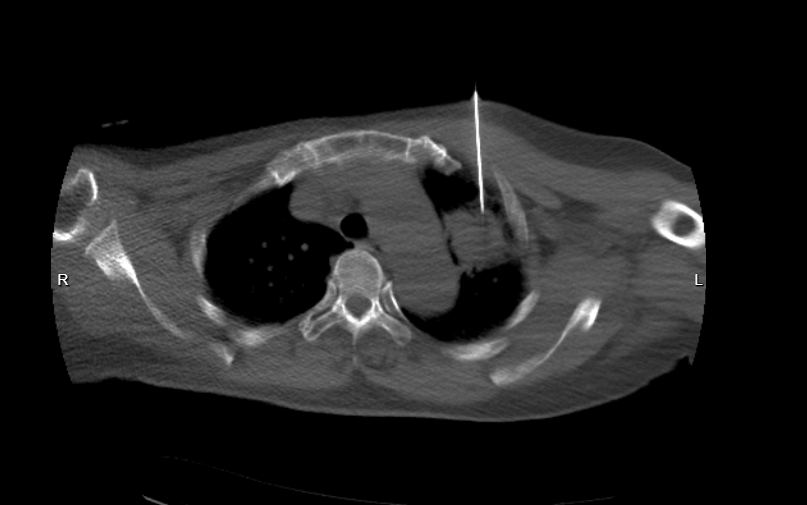

入院后,科室团队对患者既往影像、病史进行系统梳理,综合评估咯血风险及病灶特点,在充分做好术前准备和风险防控的前提下,为患者实施CT引导下经皮肺穿刺活检术。整个操作过程顺利,未出现出血、气胸等并发症,体现了团队在高风险肺穿刺方面扎实的技术功底和严谨的医疗决策能力。

肺穿刺病理结果显示:肺组织未见明显恶性肿瘤细胞,支气管及肺泡结构完整,间质纤维组织增生明显,伴大量淋巴细胞、浆细胞及中性粒细胞浸润;PAS染色局部可见疑似真菌菌丝,形态学特征符合慢性感染性病变。

结合 PET/CT 检查结果(病灶未见明显糖代谢增高)、临床表现及实验室资料,最终明确诊断为:肺曲霉菌病,而非此前高度怀疑的肺癌。